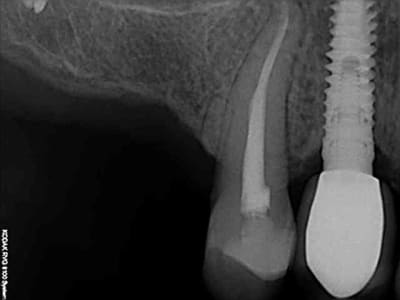

aussitôt demandé, aussitôt fait !!

(j+1 an)

R18 naqzzj - Eugenol

tu as perdu pas mal d'os!!